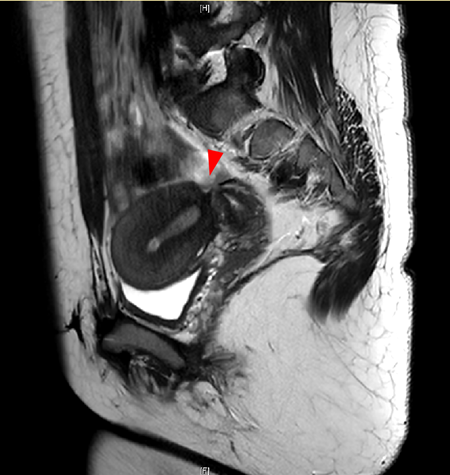

子宫重建术前盆腔核磁显示,本应完整连续的子宫体与子宫颈完全离断(红色箭头)

在妇科郭红燕主任团队带领下,韩劲松、张坤主任医师等结合病史、查体及影像学检查,发现患者子宫颈与宫体竟然在车祸中完全横断。由于当时未被发现,随着月经排出受阻,逐渐出现了闭经及经血淤积宫腔导致的痛经症状。2018年3月,患者在我院接受了腹腔镜下子宫颈-子宫体断端吻合重建术,术后患者恢复正常月经,痛经症状也明显缓解。